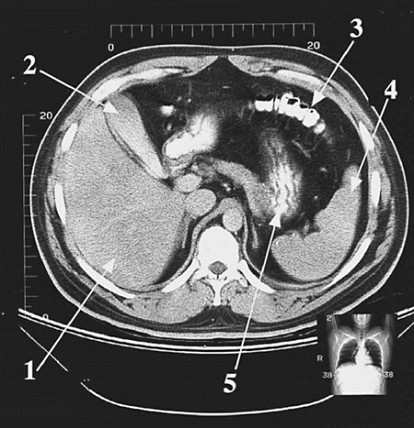

A 42-year-old female patient has to undergo emergency cholecystectomy due to intense biliary colic. The structure to be removed during the surgery is indicated in following figure by which of the following arrows?

Arrow 2 points to the gallbladder, which will be removed during the cholecystectomy (surgical removal of the gallbladder). Biliary colic may be due to impaction of a gallstone in the cystic duct, resulting in cholecystitis (inflammation of the gallbladder). Arrow 1 (choice A) points to the liver. Arrow 3 (choice C) points to the transverse colon. Arrow 4 (choice D) points to the spleen and arrow 5 (choice E) indicates the stomach, recognizable by its internal rugae.